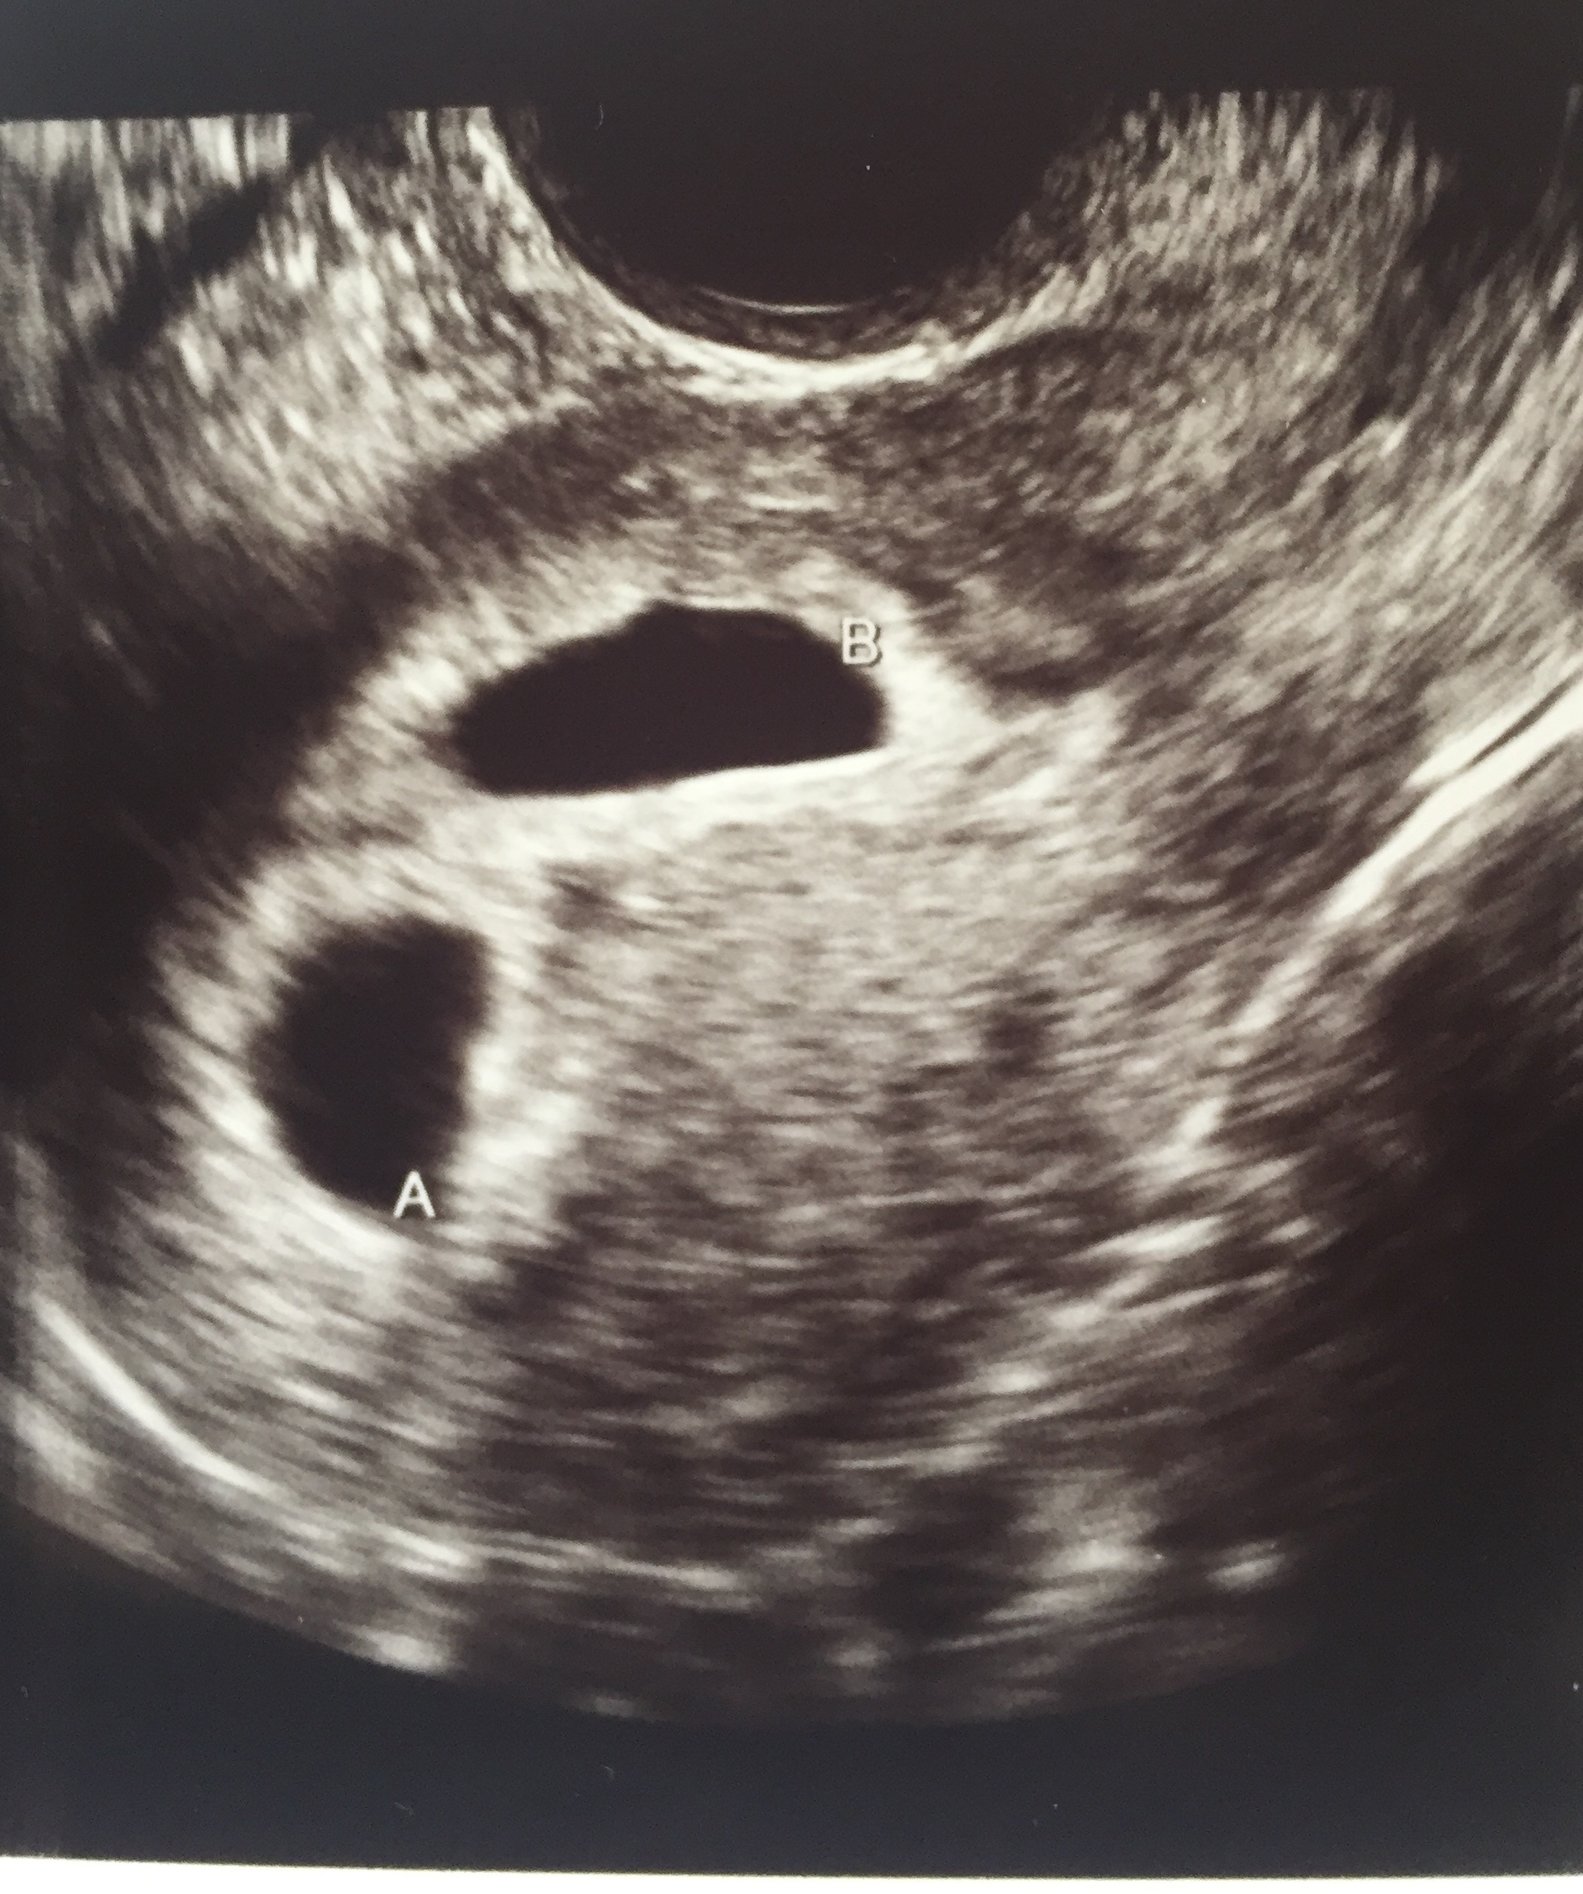

• @EmilyE13 thought your u/s was tomorrow but must be getting my dates wrong!  Congrats on your two little beans! They are beautiful and so happy you could hear the heartbeat.

• @EmilyE13 that's amazing!! Congrats! Thabks for sharing the beautifl pictures.

• @emilye13 your precious babies!!!!! I'm so glad to hear they are healthy little peanuts! <3

@EmilyE13. What beautiful sonogram pics so happy for you good luck on the healthy process of your pregnancy